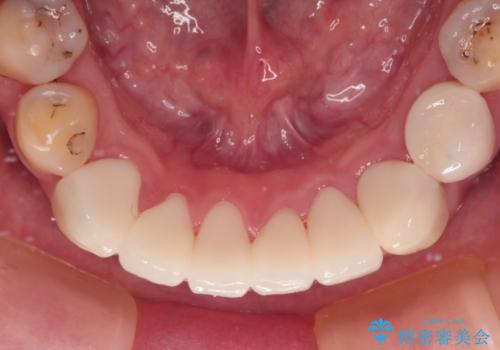

- 上下前歯や奥歯の虫歯治療を希望して来院された患者様です。

全顎的にむし歯が多く、根管治療の必要奥歯や、審美的に気になっている前歯を中心にオールセラミッククラウンにて補綴治療を行うこととしました。

歯肉移植術による根面被覆を行うかどうかは非常に悩まれていましたが、歯肉が覆われたことで長く見えていた歯の長さが整い、きれいな前歯の仕上がりとなりました。